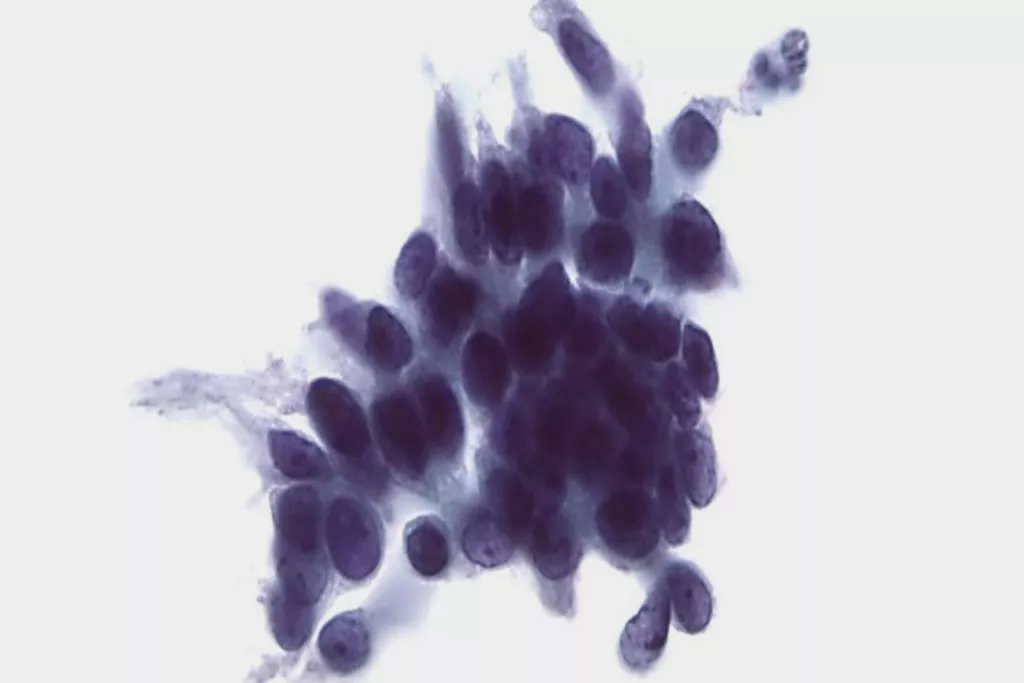

Image Gallery9

9. Images received from Cytopathology Department, Llandough Hospital, Wales